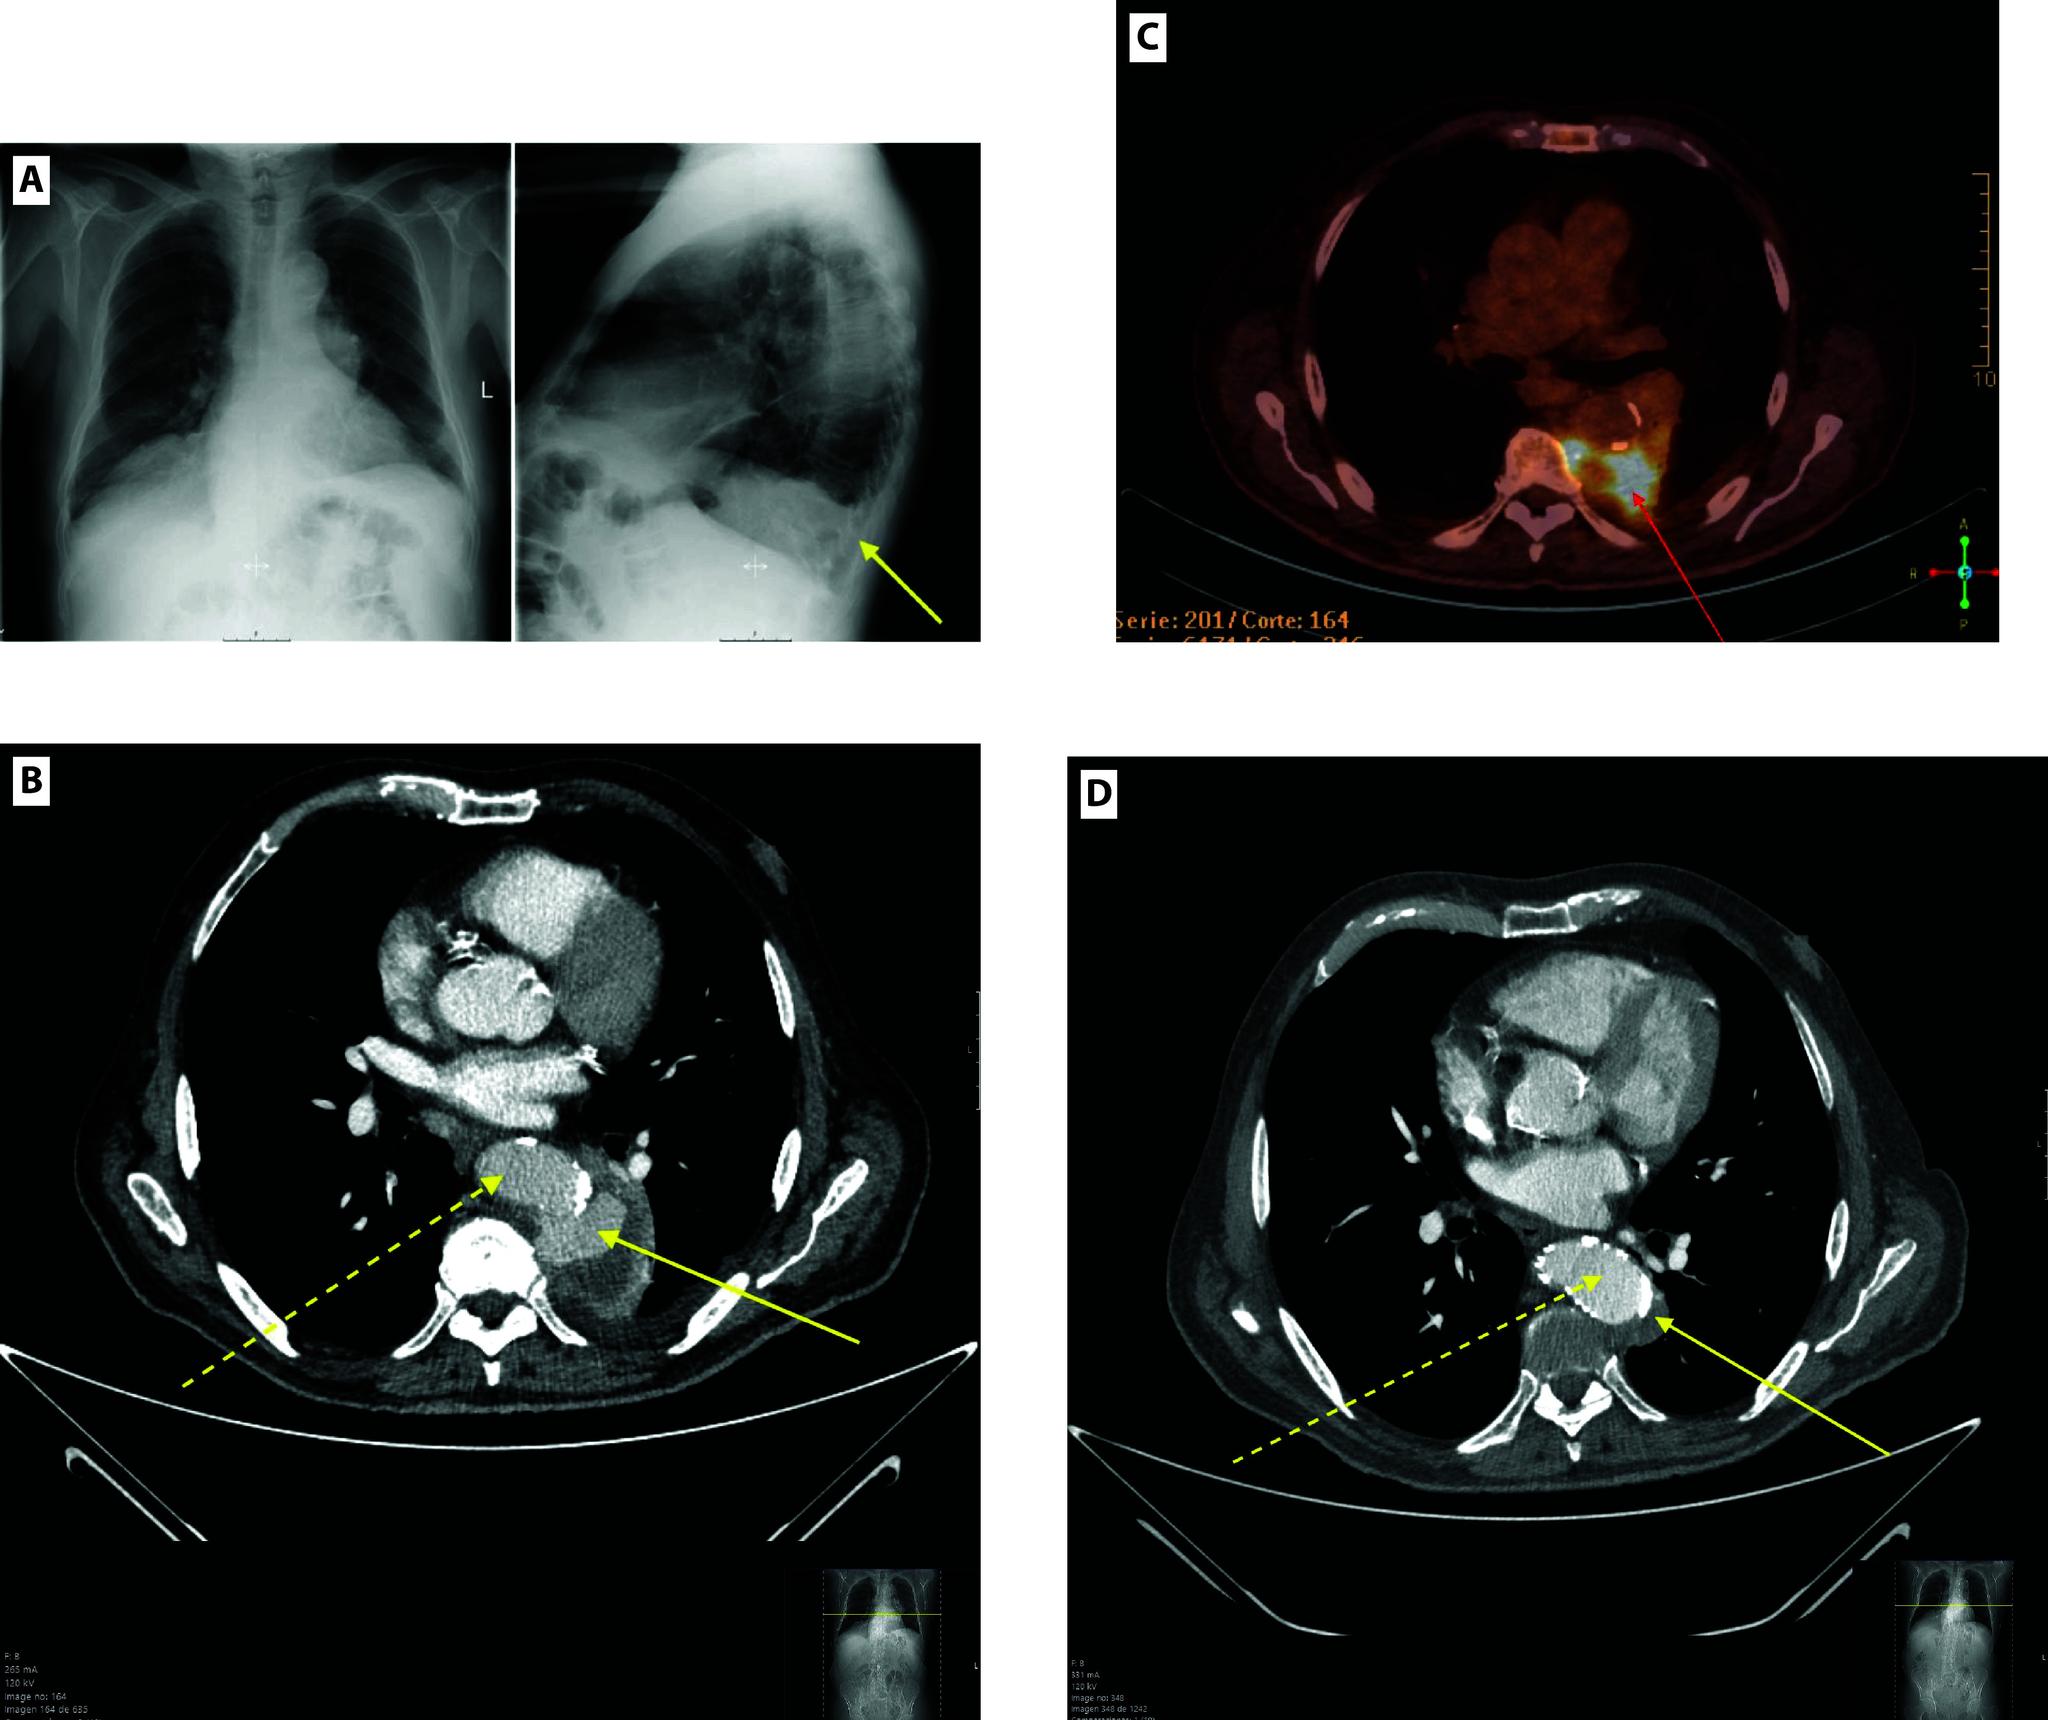

We report the case of an 81-year-old male who presented with fever and pleuritic chest pain and was initially misdiagnosed with community-acquired pneumonia. A CT scan later  revealed a saccular, ruptured thoracic aortic aneurysm. Despite antibiotic therapy, the patient developed haemoptysis, necessitating thoracic endovascular aortic repair (TEVAR). Post-procedure, the patient showed significant clinical improvement and was discharged in stable condition 45 days later.

Infected thoracic aortic aneurysms presenting as haemoptysis are exceptionally rare but life-threatening. Early clinical suspicion (manifested by haemoptysis, fever and thoracic pain) is essential, particularly in patients with risk factors such as immunosuppression or previous infections. This case emphasizes the importance of prompt diagnosis and intervention, along with the use of appropriate imaging techniques to reduce morbidity and mortality associated with this rare yet severe condition.